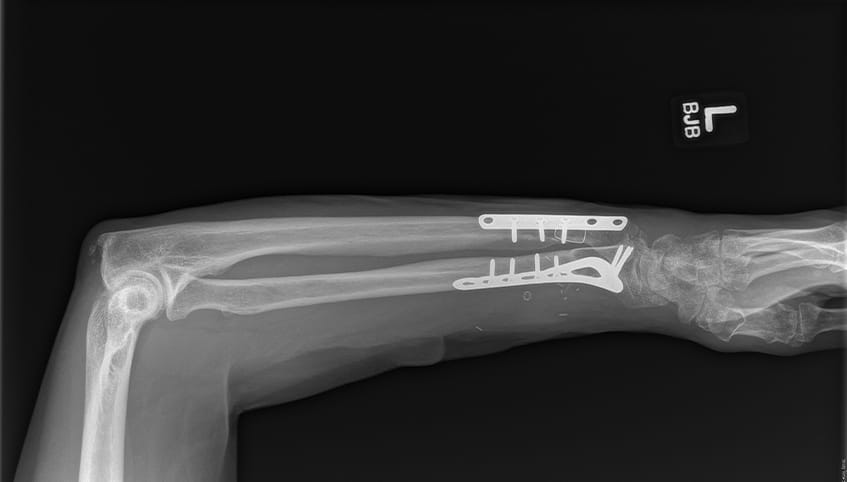

Surgeons performed Steve's surgery under a microscope. They first plated and screwed the severed bones into place and then used sutures finer than a human hair to reconnect transected nerves, veins, blood vessels and tendons.

Steve Pelgrin post surgery x-ray